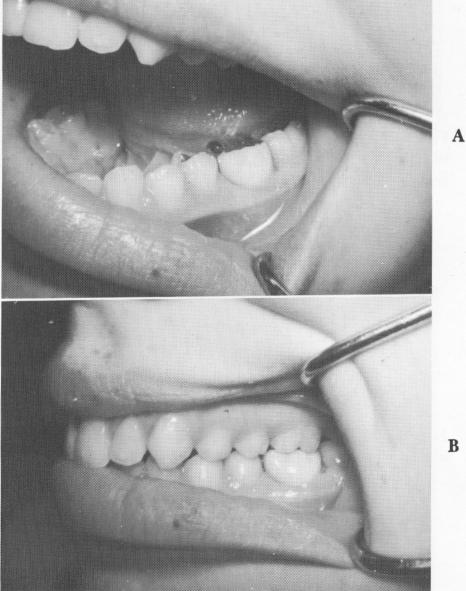

In this case, an unusual approach was taken to prevent good neighboring teeth from being sacrificed for full crown restorations. A 13-year-old girl had sagittally fractured a 6-year mandibular molar exactly in half vertically downward to the apices of the roots in a mesiodistal direction. The canals were also severed exactly in half, so that root canal therapy was impossible. The buccal half of the tooth was removed (Fig. 8-70), and a vent-plant was screwed through the bone remaining between the mesiobuccal and distobuccal roots (Fig. 8-71). The protruding shaft of the implant and the lingual half of the molar tooth were notched and locked together with acrylic (Fig. 8-72). The acrylic was prepared (Fig. 8-73) and an impression taken for a full crown gold veneer, which was cemented in position with hard cement (Fig. 8-74). A radio-

Fig. 8-74. A, A gold-and-acrylic veneer crown is cemented over the acrylic core, which locks the implant to the lingual half of the tooth. B, The occlusion must be carefully balanced.